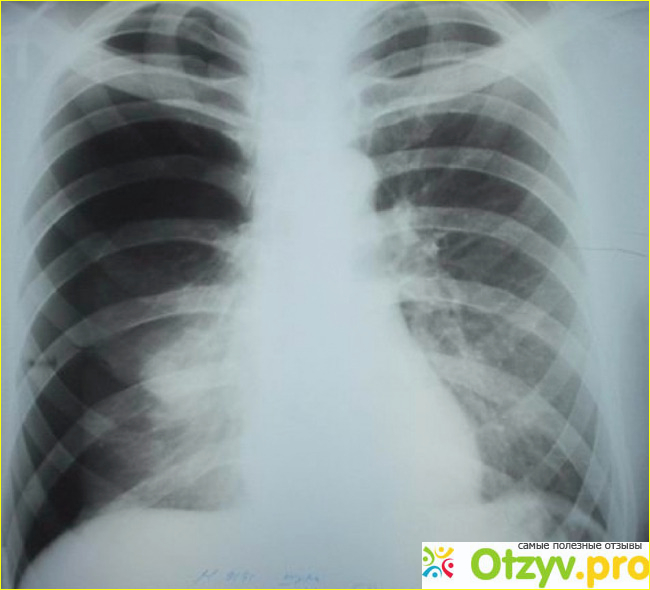

Мне изначально поставили диагноз - пневмония нижнедолевая левого легкого, так как по результатам измерения артериального давления и проверки сердцебиения у меня дыхание отставало в левой стороне значительно. Мне сказали собрать с собой необходимые вещи и сказали, что вероятнее всего вас будут ложить на продолжительный срок. Я очень сильно испугался и мы выехали в больницу, по пути мне было очень больно от наших дорог, потому что они построены по принципу кочка на кочке. Но все же мы прибыли на конечный пункт назначения. Там я прошел в отдельный кабинет и там уже сидела тот самый врач Виталий Казакевич. Он меня направил на прохождения рентгена, и на снимках выявилось что у меня спонтанный пневмогидроторакс. В левом легком, а точнее в плевральной полости скопилось много жидкости и воздуха. Это результат моей простуды и то как я ее потом на ногах перенес, моя конечно вина в случившемся, но мне надо было исправлять данную ситуацию. И тут мне этот врач сказал, хотите ли вы сегодня делать пункцию легких или придете завтра. Не понял, как можно вообще такие вопросы задавать, если он прекрасно видит, как я стою на ногах. Конечно же я без раздумия согласился на хирургическое вмешательство.